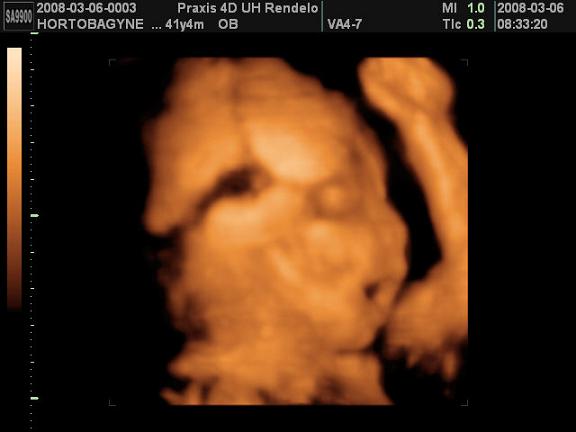

Sziasztok!

Most jöttünk meg a Praxisból, nagyon jó volt :lol: A doki mindjárt mondta hogy nem valami jól fekszik baba a látvány szempontjából de azért csinált pár képet profilból. Nem sokat mocorgott de azt többször láttuk hogy éppen ásít :D Anna jól viselte, úgy helyezkedtek apjával hogy ne azt lássa, hogy velem mit csinálnak, hanem a monitort. Érdeklődve nézegette a babát, bár a tekintetén látszott hogy kicsit furcsállja a látványt :lol: . A doki megerősítette:150% hogy fiú, bár nem tudta jól megmutatni mert Öcsike rajta ült a fenekén, de azt mondta szakember számára biztosan látszik a herezacskó. Persze a genetika eredménye alapján már tudtuk, de a férjem mégis kicsit kételkedett mert ezt nem adták ott írásba, csak szóban mondták... :wink:

És a lényeg persze hogy a vizsgálat alapján mindent rendben talált :D Teszek fel képet, remélem kivehető nagyjából az arca, és a keze :D